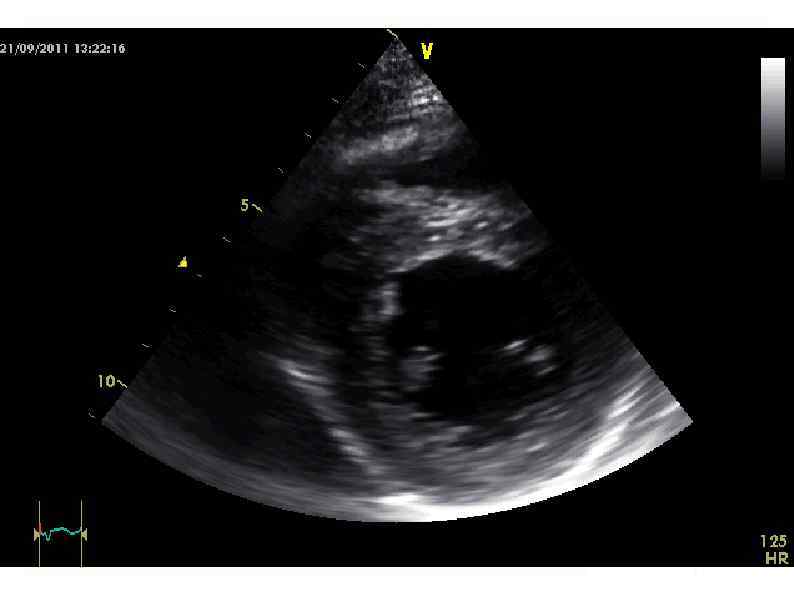

Эхо-КГ 16/09/11 (ЧСС - 140 -150/мин!) Диффузный гипокинез стенок левого желудочка, ФВ 55%. Митральная Эхо-КГ 16/09/11 (ЧСС - 140 -150/мин!) Диффузный гипокинез стенок левого желудочка, ФВ 55%. Митральная регургитация II степени, трикуспидальная регургитация II степени. Признаков легочной гипертензии нет.